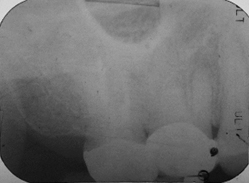

術前PANO照

我們先收集術前X光片與電腦斷層,以利黃醫師評估診斷。經由X光片可發現該顆牙齒根管以於多年前治療過,並且製作了假牙配戴。另從電腦斷層上也發現根尖部分有發炎反應。

(術前X光片)